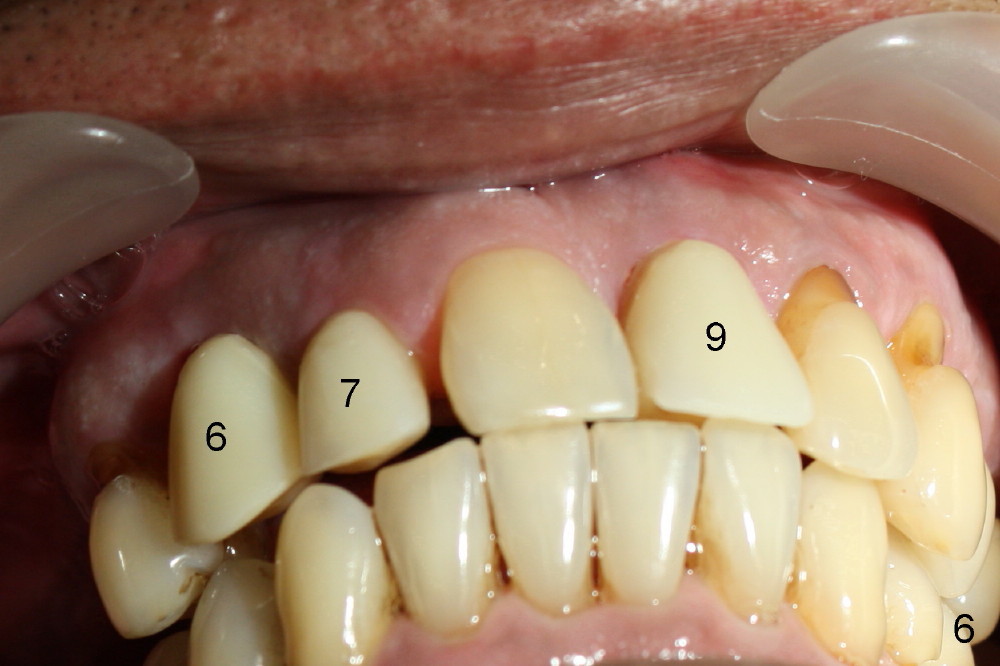

Fig.6 shows these provisionals 1 week postop. The patient is happy with the result. His diet is confined to soft food. The provisional at the site of #9 is slightly mobile.

The provisional of #9 is still wiggling a little bit buccolingually. It is probably due to loose connection between the implant and the abutment, although follow up PAs do not support it (Fig.7,8; ^: bone graft at the time of immediate implants).